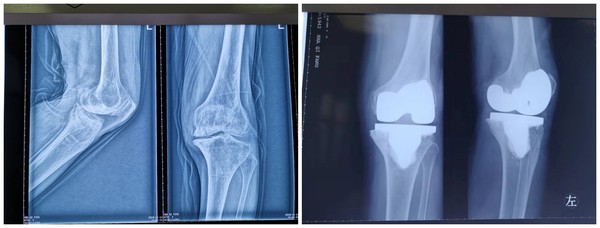

11月30日,我院骨一科团队为一名膝关节炎患者成功实施了“左膝关节人工全膝关节表面置换术”,术后疗效显著,解决了患者多年的膝关节疼痛及行走问题。

患者,76岁,因患双膝关节骨性关节炎12年,疼痛难忍行走困难,于11月27日入住我院骨一科。夏建军主任医师与科内人员针对手术的风险、并发症、预后等情况进行反复分析讨论、全面评估,制定科学周密的手术方案。最终决定施行人工膝关节置换术。手术当日在夏建军主任医师的带领下手术团队历时2小时,成功完成了我院首例全膝关节置换手术。术后患者生命体征平稳,各项指标正常。

该例手术为我院首例自主完成的全膝关节置换术。标志着我院在新技术新项目上取得的突破和进步。